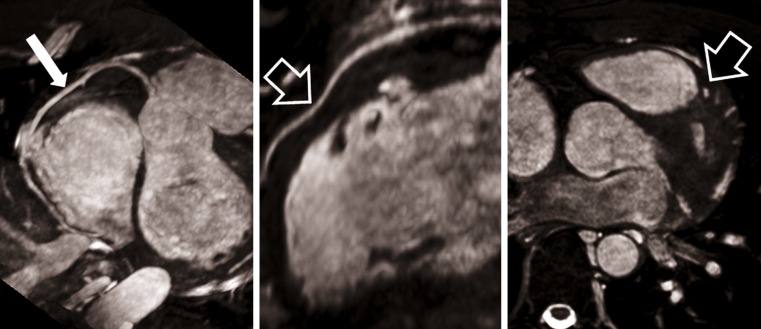

MRI of myocardial viability has substantially changed over the last two decades. The evaluation of late gadolinium enhancement (LGE) techniques has pushed the envelope for the clinical routine assessment of myocardial viability using MR techniques. Before the use of LGE imaging assessment of myocardial viability using MR approaches has been based on low-dose (5-10 μg/kg/min) dobutamine stress cine MRI [107, 108]. Early studies by Kim et al. [109, 110] evaluated the correlation of LGE of the myocardium and the presence of myocardial viability and necrosis in animal models. In early patient studies, the impact of this imaging technique on the prediction of patient outcome after myocardial infarction and revascularisation procedures has been demonstrated [111, 112]. LGE imaging offers the ability to assess the transmural extent of residual viability in patients after myocardial infarction. As a major pre-requisite in the use of LGE techniques in myocardial ischaemia, it has to be considered that the extent of myocardial infarction is typically related to coronary artery supply territories and that the development of necrosis starts at the subendocardial level propagating towards the epicardial border over time (Fig. 8) [113].

Fig. 8.

Differentiation of transmural extent of myocardial infarction using late gadolinium enhancement (LGE) imaging. While the left image (a) demonstrates an almost transmural LGE consistent with only minor residual viable tissue, the patient on the right (b) only suffered from a smaller subendocardial myocardial infarction in the RCA territory